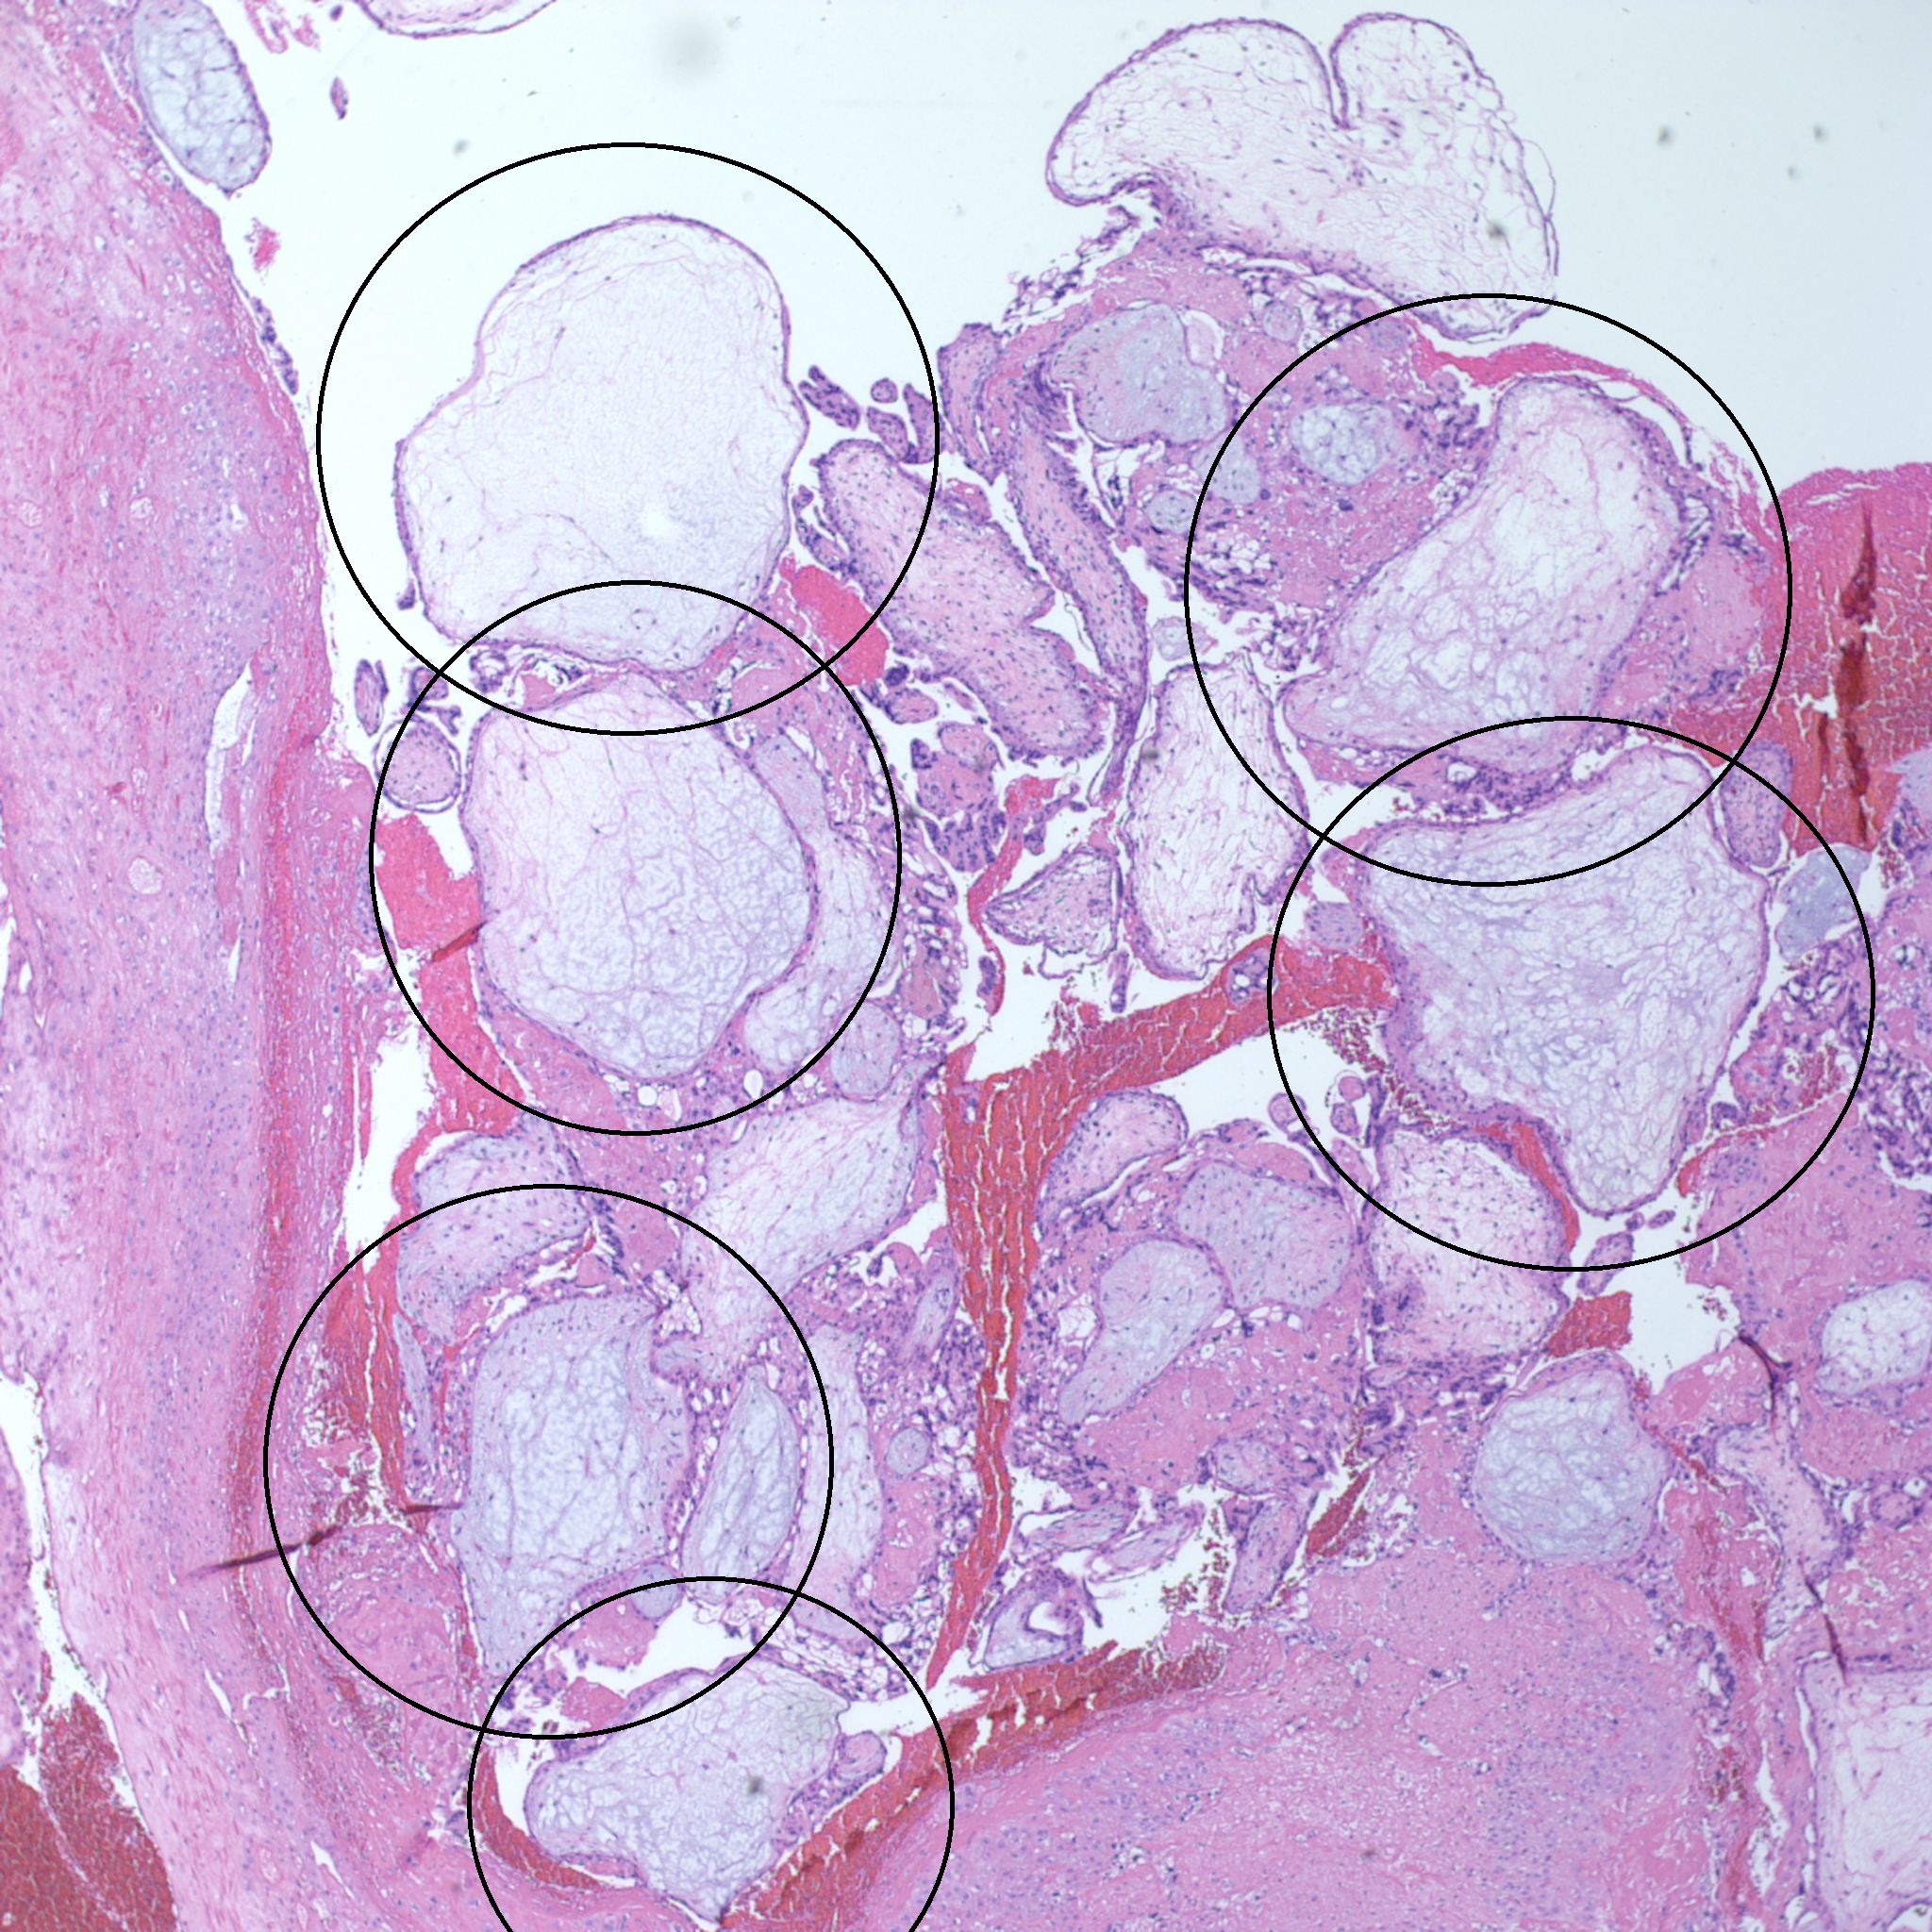

At low power we see throughout the specimen that numerous enlarged hydropic chorionic villi are present (circles).